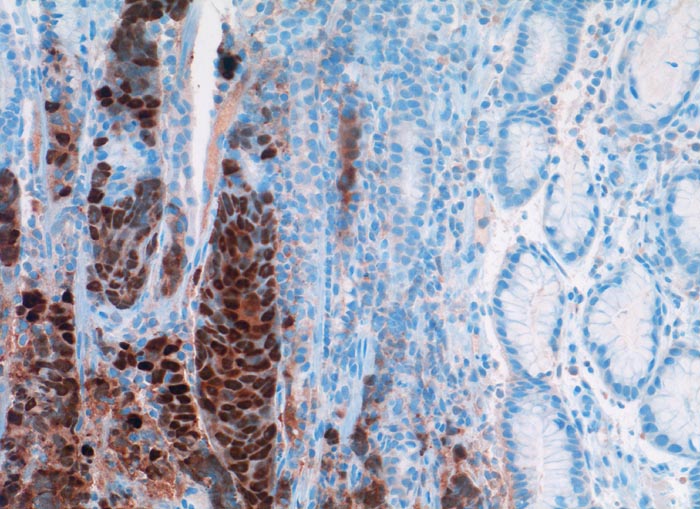

l/ Östrogenrezeptor

Östrogenrezeptor

Anfärbung:

Zellkern. Zytoplasmafärbung ist unspezifisch.

Reaktion im Normalgewebe:

Epithel und Stromazellen von Vulva und Vagina. Endometrium. Mammaepithelien.

Reaktion in Neoplasien:

Folgende Tumoren können Östrogen- und/oder Progesteronrezeptoren exprimieren:

Folgende Tumoren exprimieren nie Östrogenrezeptoren:

Kolorektales Adenokarzinom

Nicht-kleinzelliges Bronchuskarzinom

Hepatozelluläres Karzinom

Identifikation von Mammakarzinomen, die möglicherweise auf eine Hormontherapie ansprechen.